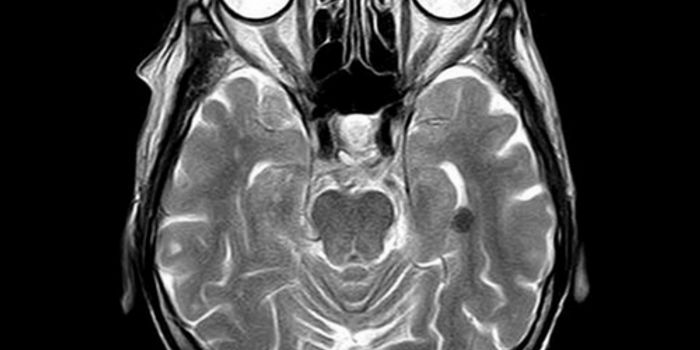

APR 09, 2015NeuroscienceA new study by UNC researchers, based on MRI brain scans of 152 infants, found disruptions in functional connectivity wi ...